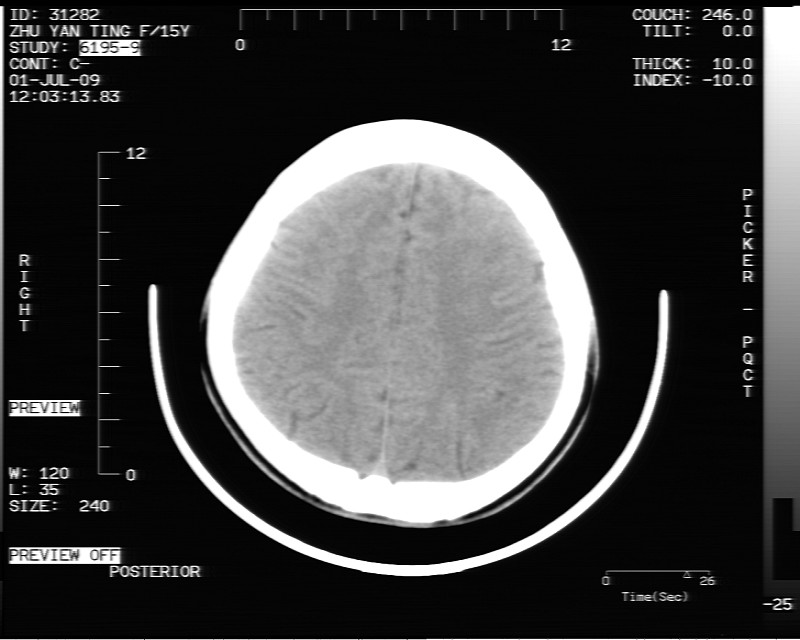

以下是引用余辉在2009-7-1 17:20:00的发言:[br]病变ct值-20至-80[br]考虑脑内脂肪瘤破裂,瘤主体应该在右侧桥小脑角池及鞍上池[br]鞍上池病灶面积较大,ct值应该能够测准,应此病灶应该就是脂肪密度,病灶密度有ct值-20至-80hu,为成熟脂肪密度,因此考虑脂肪瘤,也不除外其他含成熟脂肪的病灶[br]皮样囊肿密度应该稍高一点